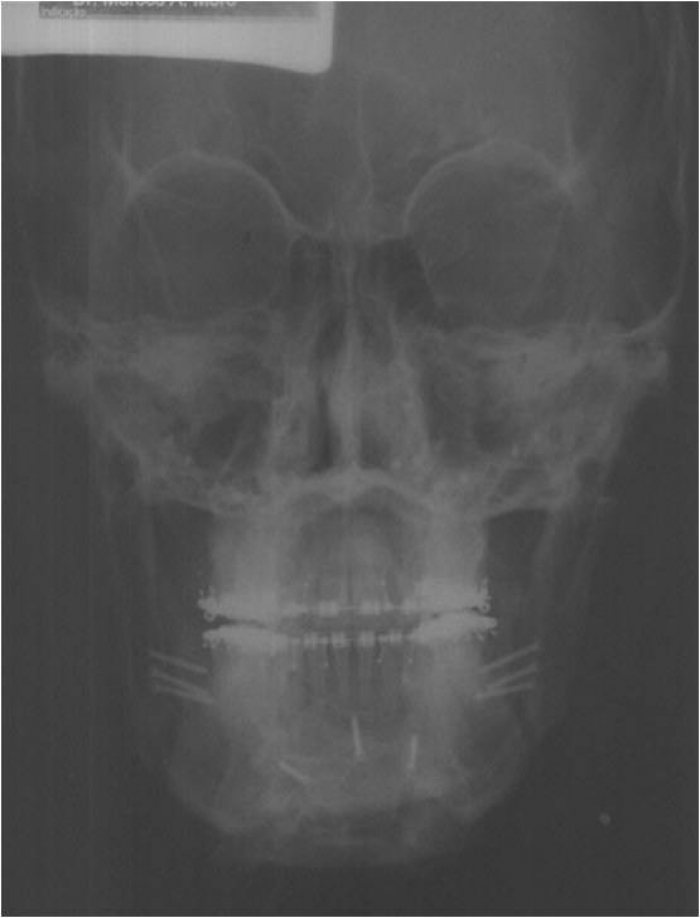

Telerradiografia frontal inicial